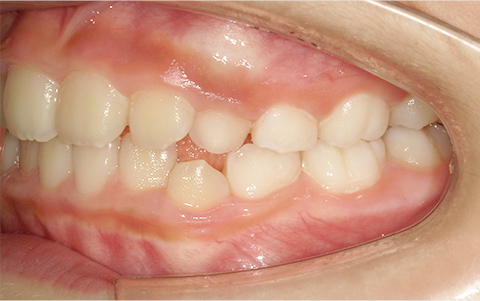

このような歯並びで

お悩みではないですか?

歯並びが悪い

症例